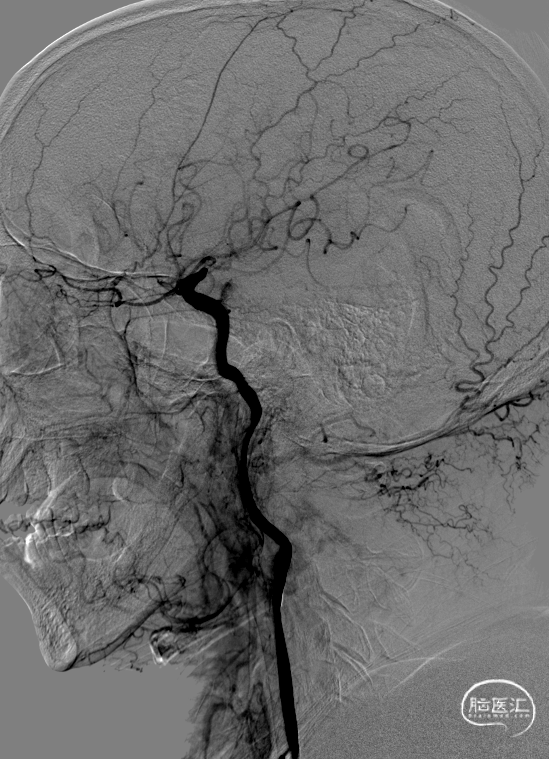

术前DSA右侧经总动脉造影提示:前交通动脉开放,右向左代偿,左侧大脑中动脉血流慢。

左侧经总动脉动脉造影显示:左侧颈内动脉末端极重度狭窄。

正位

侧位